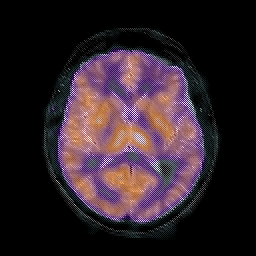

AIDS dementia: overlay -- Slice #9

[Home][Help][Clinical][Tour 1] Slice 9